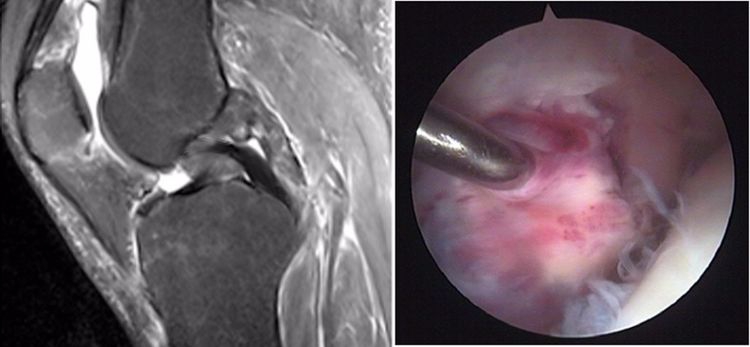

后交叉韧带撕裂的MRl直接表现:

1.韧带实质部撕裂 (根据表现分为3级)

2.后交叉韧带股骨附丽点撕脱(不多见)

后交叉韧带损伤的MRI分级:

Grade1:韧带内损伤,无长度改变。

Grade2:韧带内损伤并长度延长。

Grade3:完全性韧带撕裂。